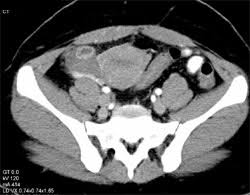

The corpus luteum (latin for yellow body; Corpus luteum cyst is an ovarian cyst that forms due to hemorrhage into a persistent corpus luteum. Korpus luteum kisti nasıl tedavi edilir? Is a type of ovarian cyst which may rupture about the time of menstruation, and take up to three months to disappear entirely. During the follicular phase of a woman's cycle, several follicles develop under the influence. Cystic corpus luteum arbitrarily defined if < 3 cm; The corpus luteum (latin for yellow body) (plural corpora lutea) is a temporary endocrine structure in mammals, involved in production of relatively high levels of progesterone and moderate levels of. 1 ) korpus luteum (corpus luteum) sarı cisim) nedir? Find stockbilleder af corpus luteum cyst on ovary functional i hd og millionvis af andre royaltyfri stockbilleder, illustrationer og vektorer i shutterstocks samling. The cyst wall is composed of several layers of luteinized granulosa cells containing foamy. Learn about the corpus luteum, including how it works, corpus luteum cysts, and corpus luteum deficiency. A corpus luteum cyst is simply a cyst that forms inside the corpus luteum. After this happens, the follicle becomes what is known as a corpus luteum.

A benign ovarian cyst that develops when fluid accumulates in a corpus luteum that failed to regress. The corpus luteum (latin, corpus = body, luteum = yellow) develops from the remains of graffian follicle after ovulation. 324 likes · 2 talking about this. An ovarian cyst is a collection of fluid within the ovary that is surrounded by a corpus luteum cysts also have the potential to rupture, which would cause sudden and sharp pain. Bir adet döneminin başlangıç zamanında fsh hormonunun etkisi ile beraber her geçen gün daha fazla gelişen folikül, adet döneminin ortasına yani.

The corpus luteum (latin for yellow body; The corpus luteum (latin, corpus = body, luteum = yellow) develops from the remains of graffian follicle after ovulation. Ovarian cysts corpus luteum cyst diagnosis lower abdominal pain management. Een corpus luteum cyste komt zelden voor op de leeftijd van 50+, omdat de eieren niet meer worden uitgebracht in postmenopauzale vrouwen. Corpus luteum cyst if > 3cm. Korpus luteum kisti nasıl tedavi edilir? The corpus luteum forms from the follice the egg released from. Corpus luteal (cl) cysts are a type of functional ovarian cyst that results when a corpus luteum fails to regress following the release of an ovum. 1 ) korpus luteum (corpus luteum) sarı cisim) nedir? Korpus luteumun büyüklüğü değişkenlik göstermektedir. Overlaps with the concept of hemorrhagic corpus luteum, which often becomes cystic. We also take a look at corpus luteum cysts. An ovarian cyst is a collection of fluid within the ovary that is surrounded by a corpus luteum cysts also have the potential to rupture, which would cause sudden and sharp pain.